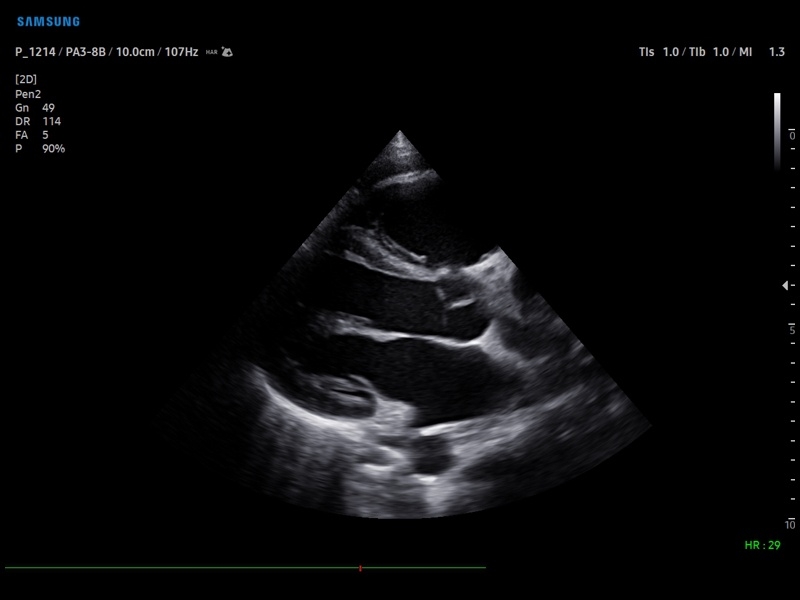

Система Samsung Medison V8 обеспечивает высококачественную диагностику в различных областях медицины:

• Кардиология

• M - одномерный режим для исследования сердца, анатомический М-режим (необходим кардиопакет), CM - цветной М-режим (необходим кардиопакет).

• Кардиопакет: тканевый допплер (TDI) + анатомический М-режим + цветной М-режим (CM) + программное обеспечение.

• Пакет кардиологических исследований.

М-режим:измерение диаметра аорты, передне-заднего размера ЛП, толщины МЖП (систолическая и диастолическая), толщины ЗСЛЖ (систолическая и диастолическая), размеров ЛЖ и ПЖ (систолический и диастолический), ФВ (Teichholz).

B-режим:измерение диаметра аорты (восходящей, дуги, нисходящей, на уровне синусов Вальсальвы, на уровне створок аортального клапана), определение размеров ЛП и ПП (максимальный, минимальный, систолический, диастолический, переднее-задний, верхнее-нижний, медиально-латеральный), расчет объемов ЛП и ПП, объемов ЛЖ (метод "Площадь-Длина", метод дисков (Simpson)), массы миокарда ЛЖ, индекса массы миокарда ЛЖ.

CD-режим (ЦДК):измерение радиуса ПФСМР (PISA), полуколичественная оценка трансмитрального, транстрикуспидального, трансаортального и транспульмонального кровотока (оценка регургитации), оценка аномальных сбросов крови через МПП И МЖП.

PW-режим (импульсно-волновой допплер):автоматическая, полуавтоматическая и ручная трассировка допплеровского спектра митрального, аортального и трикуспидального клапанов, клапана легочной артерии, кровотока в выходном тракте ЛЖ и ПЖ (пиковая/средняя скорость, пиковый/средний градиент давления, время изоволюметрического расслабления ЛЖ, время ускорения, замедления, выброса), оценка кровотока легочных и печеночных вен.

CW-режим (постоянно-волновой допплер):программы расчета работы митрального, аортального и трикуспидального клапанов, клапана легочной артерии.

TD-режим (тканевой допплер):количественная оценка локальной сократительной функции стенок ЛЖ и ПЖ.